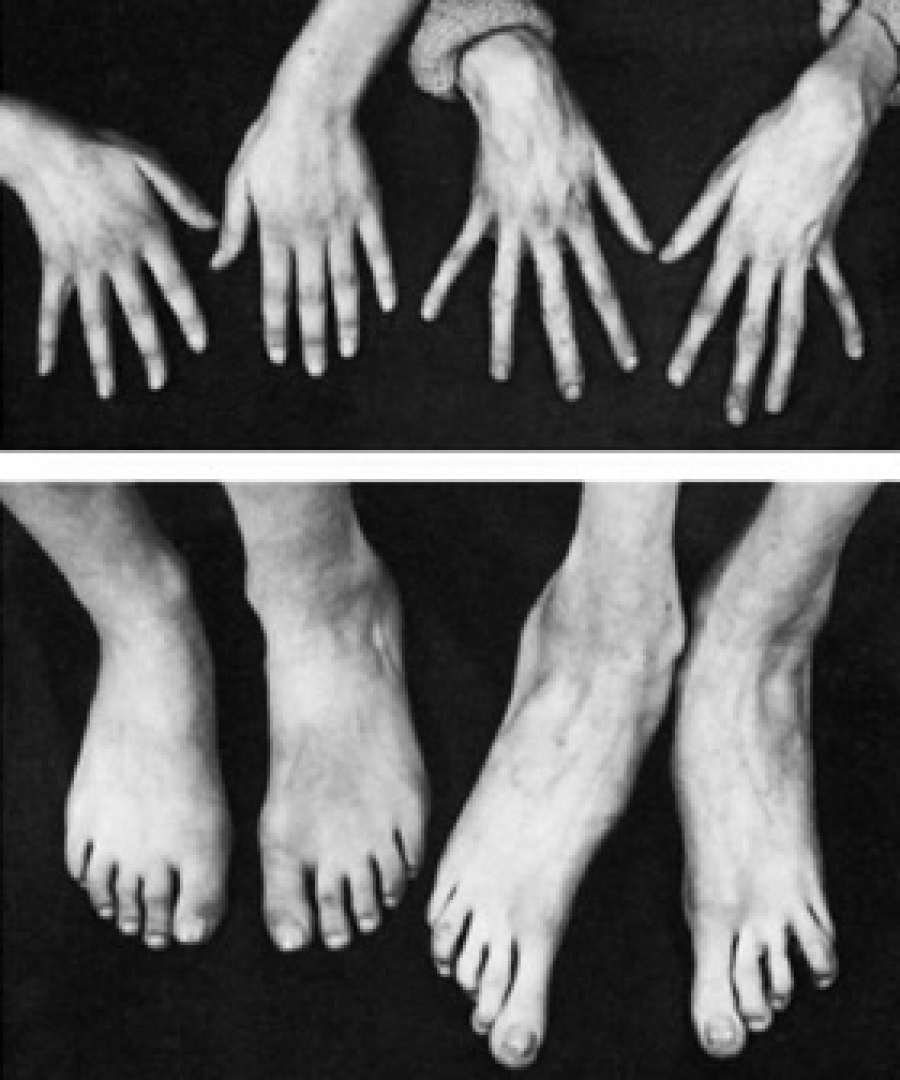

Neonatalnaya forma sindroma marfana klinicheskoe opisanie i kompleksnyj podhod k diagnostike i lecheniyu tema nauchnoj stati po klinicheskoj medicine chitajte besplatno tekst nauchno issledovatelskoj raboty v elektronnoj biblioteke kiberleninka (Тип файлу jpg)

Neonatalnaya Forma Sindroma Marfana Klinicheskoe Opisanie I Kompleksnyj Podhod K Diagnostike I Lecheniyu Tema Nauchnoj Stati Po Klinicheskoj Medicine Chitajte Besplatno Tekst Nauchno Issledovatelskoj Raboty V Elektronnoj Biblioteke Kiberleninka

Neonatalnaya forma sindroma marfana klinicheskoe opisanie i kompleksnyj podhod k diagnostike i lecheniyu tema nauchnoj stati po klinicheskoj medicine chitajte besplatno tekst nauchno issledovatelskoj raboty v elektronnoj biblioteke kiberleninka (Тип файлу jpg)

Neonatalnaya Forma Sindroma Marfana Klinicheskoe Opisanie I Kompleksnyj Podhod K Diagnostike I Lecheniyu Tema Nauchnoj Stati Po Klinicheskoj Medicine Chitajte Besplatno Tekst Nauchno Issledovatelskoj Raboty V Elektronnoj Biblioteke Kiberleninka